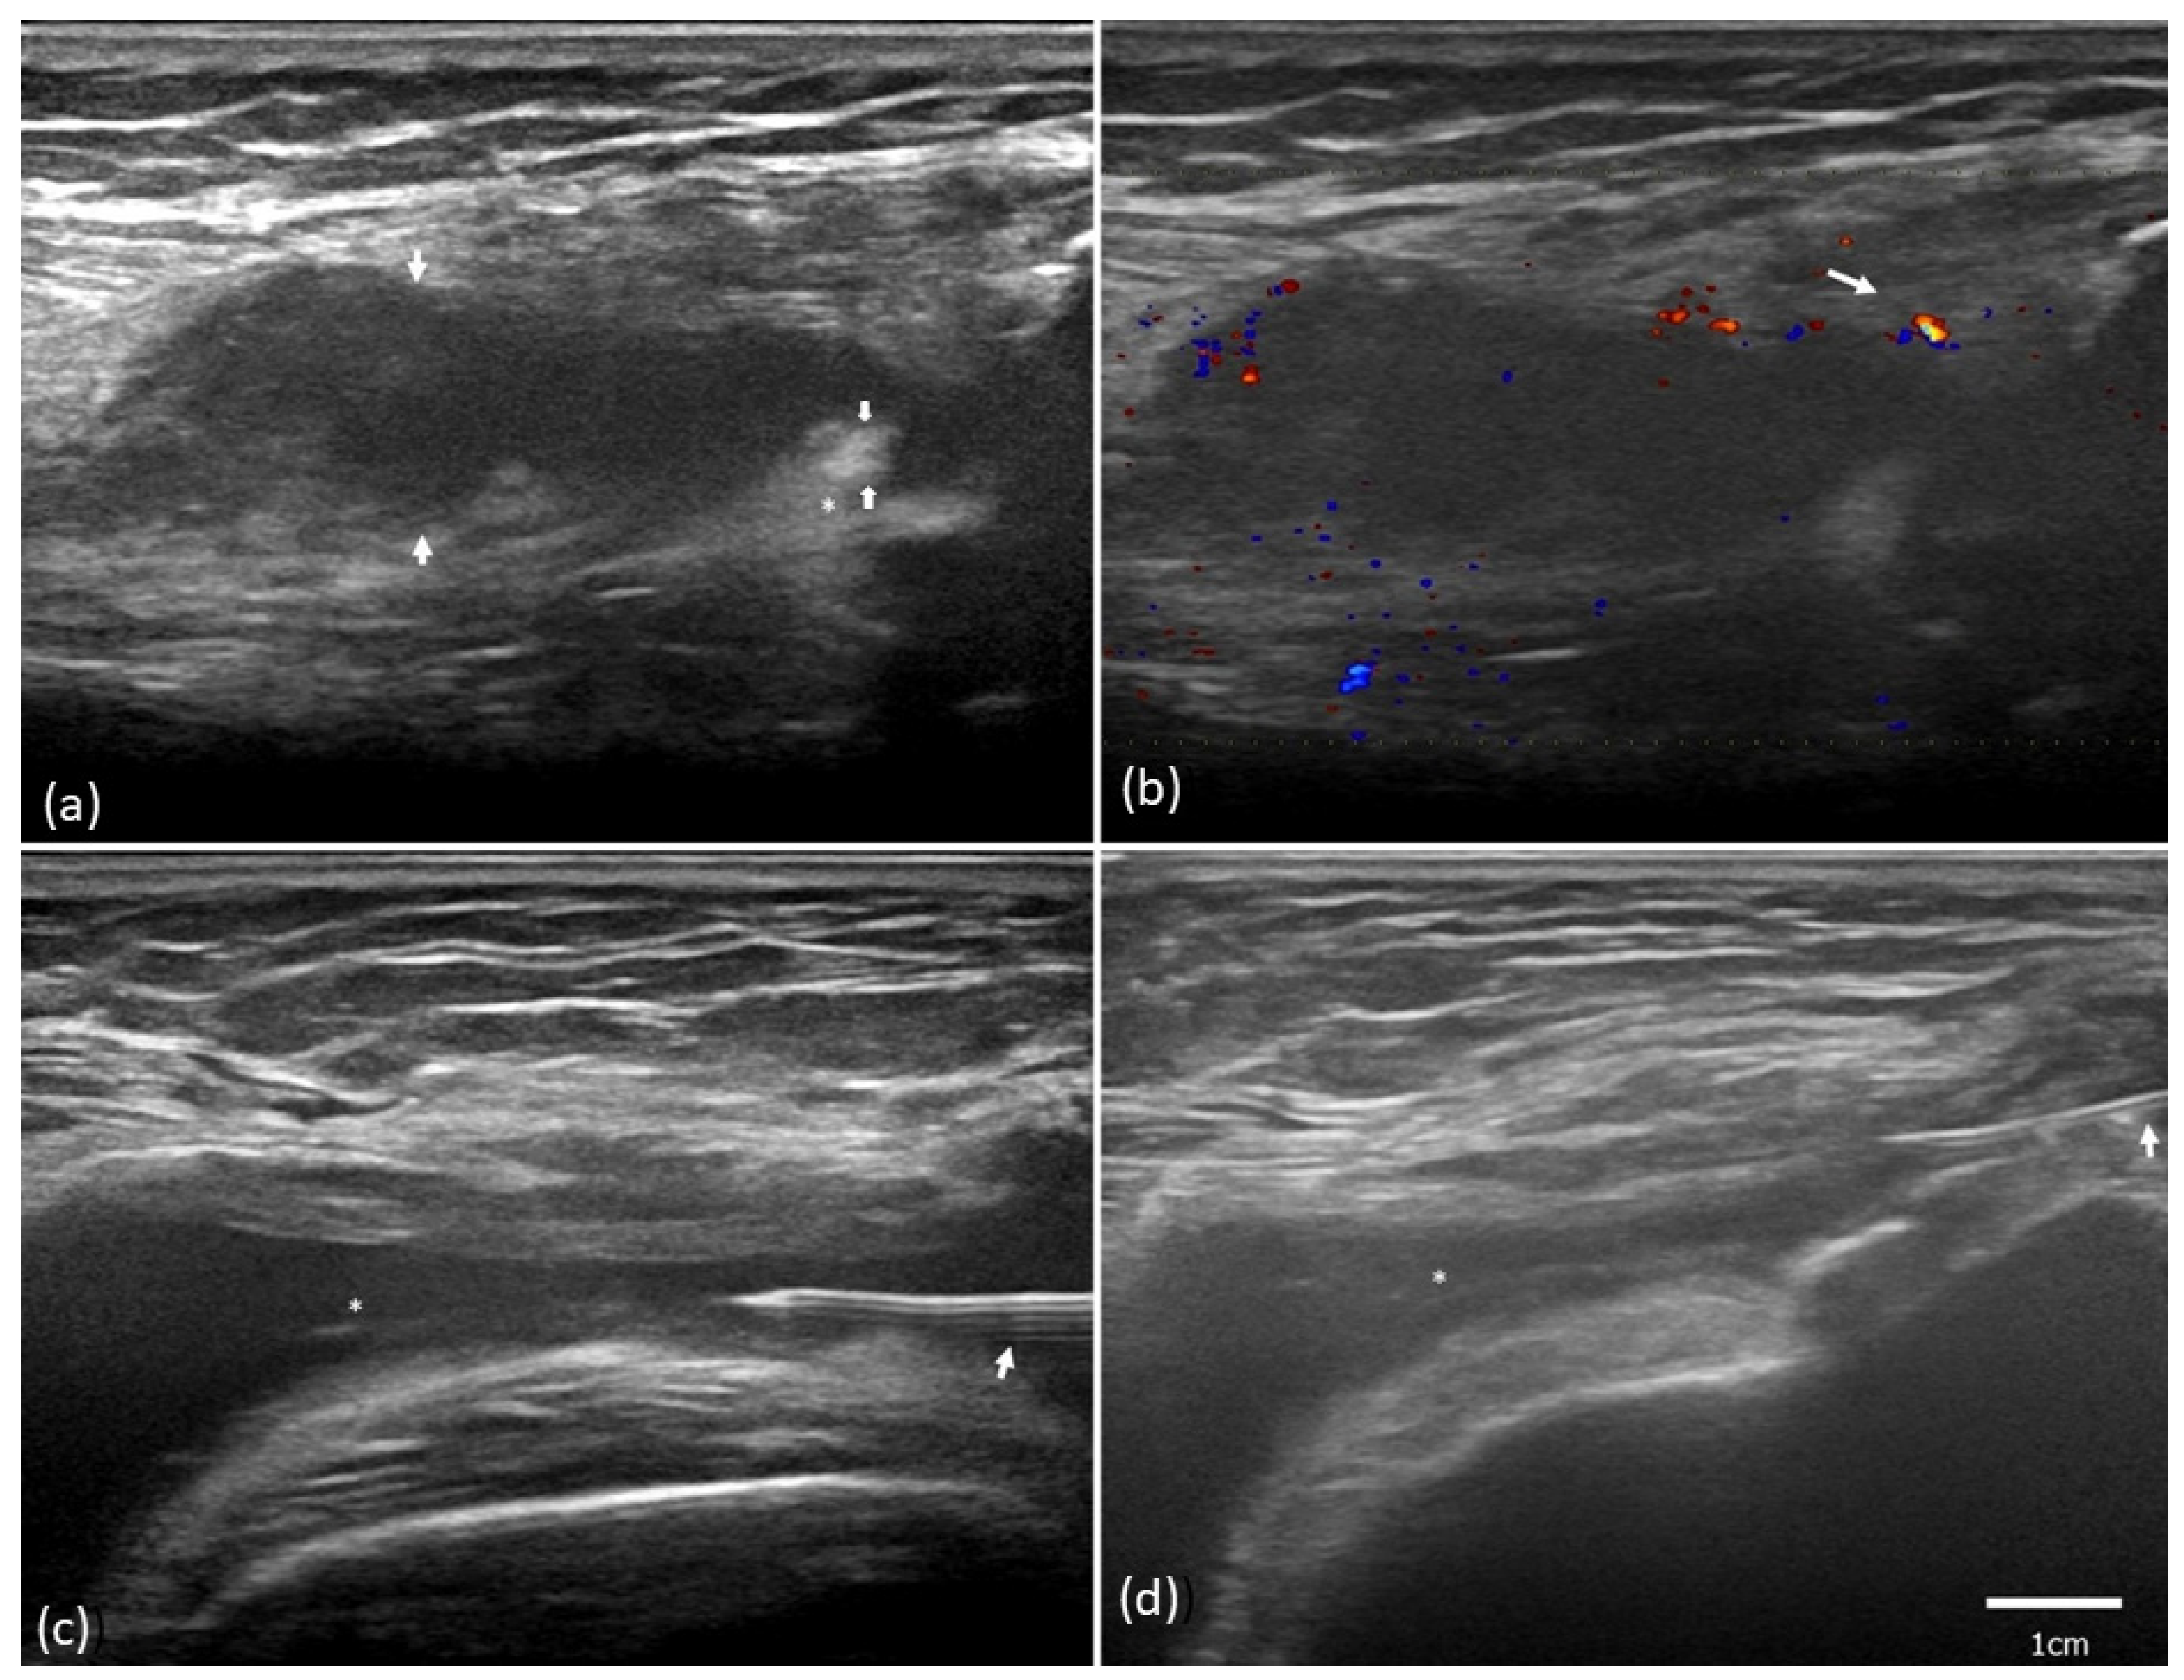

2.1. Patient Characteristics

2.2. Ultrasound Synovial Outcome

4.3. Ultrasound Evaluation